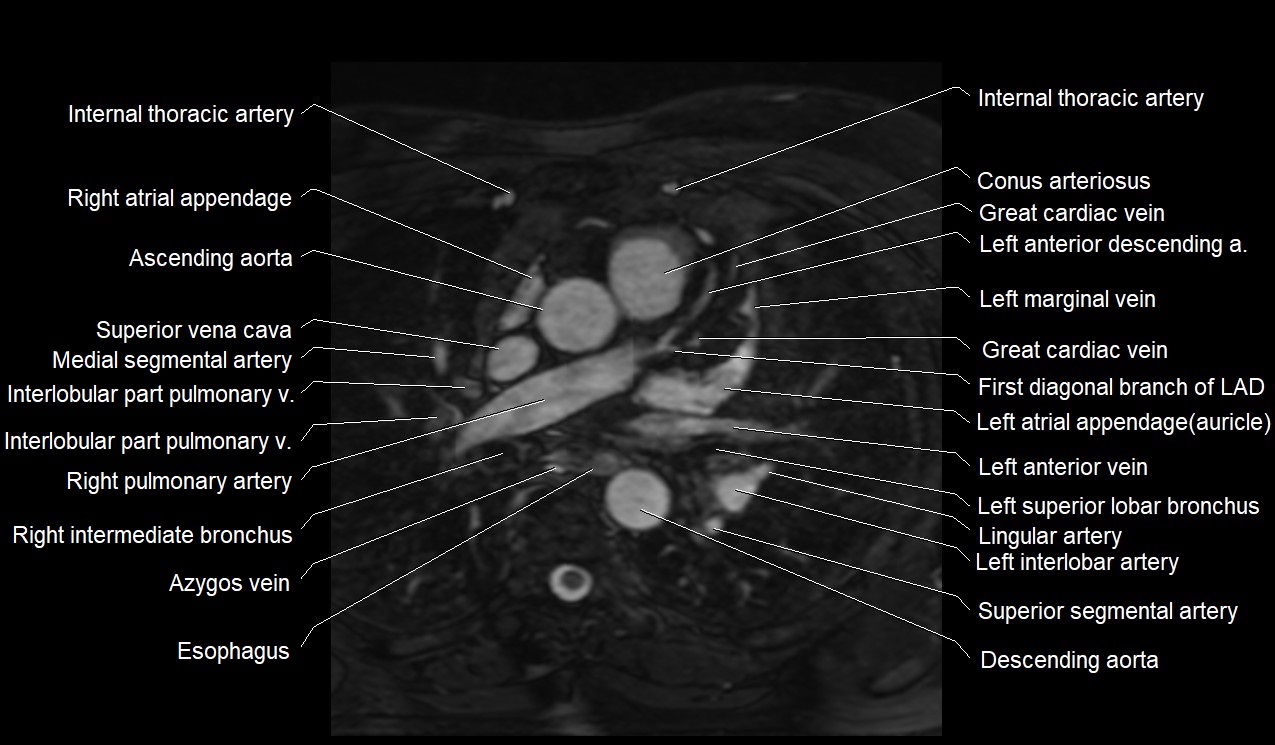

MRI image